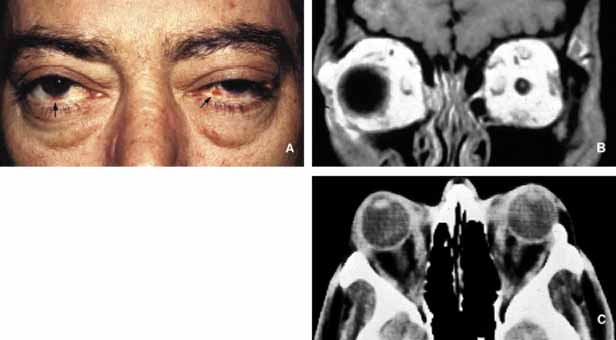

Sjögren syndrome (SS) consists of a triad of symptoms including dry eyes (keratoconjunctivitis sicca), dry mouth (xerostomia), and “dry joints” (arthritis).120 Primary SS is not associated with other connective tissue diseases; however, secondary SS symptoms overlap with the manifestations of systemic lupus erythematosis, polymyositis, polyarteritis nodosa, scleroderma, and rheumatoid arthritis.121 Like many other autoimmune diseases, SS does not have a clear cut etiology, however, primary SS is considered a mononuclear inflammatory vasculopathy closely linked to HLA-DR3 and HLA-DRw52; secondary SS associated with rheumatoid arthritis is linked to HLA-DR4.122 Many viruses, including Epstein-Barr, CMV, HIV, and hepatitis-C, have been reported to have an etiologic role in SS. Immune complex formation and deposition are considered to be the physiopathology of cutaneous and ocular vasculitis.123

Histopathology of the conjunctiva as well as the lacrimal gland is nonspecific consisting of lymphocytic and plasma cell infiltrates surrounded by eosinophilic basement membrane like material (Table 2). These units are called epimyoepithelial islands and are considered to be diagnostic of SS.124 Lacrimal gland also reveals acinar atrophy and increased fibrosis surrounding the ductules125 (Fig. 12). Diagnosis of SS is based on minor salivary gland biopsy rather than the biopsy of the lacrimal gland, because the latter procedure is more invasive and carries a higher morbidity.126

Fig. 12 Sjögren disease. A pateint with bilateral enlargement of lacrimal glands that was involving the left side more than the right (A,B). Minor salivary gland biopsy from the lower lip revealed infiltration of eosynophils, lymphocytes and plasma cells. The biopsy was sufficient to make the diagnosis combined with the clinical picture. The same patient developed orbital lymphoma, which is depicted in frame B, 3 years after the diagnosis of Sjögren disease.

Keratoconjunctivitis sicca is the most common presentation of SS in the eye occurring in approximately 90% of patients. Diminished tear meniscus and decreased tear break up time (BUT) with diminished tear production documented with Schirmer strips are common findings. Less commonly, patients develop episcleritis/scleritis in primary type of SS.127 Because of peripheral and central nervous system involvement, optic neuritis and internuclear ophthalmoplegia may be seen in these patients. From the orbital standpoint, the asymmetrical presentation of the disease may be confused with an orbital lymphoma or sarcoidosis. In most cases, however, the disease presents with bilateral enlargement of the lacrimal glands and with the presence of other symptomatology SS is easy to diagnose (Fig. 12). It should be kept in mind, however, that SS patients have an increased risk of developing B-cell lymphomas in the salivary glands and cervical lymph nodes. This association was not found to be true for the lacrimal gland. However, orbital lymphoma that may mimic the presentation of SS should always be considered in the differential diagnosis.